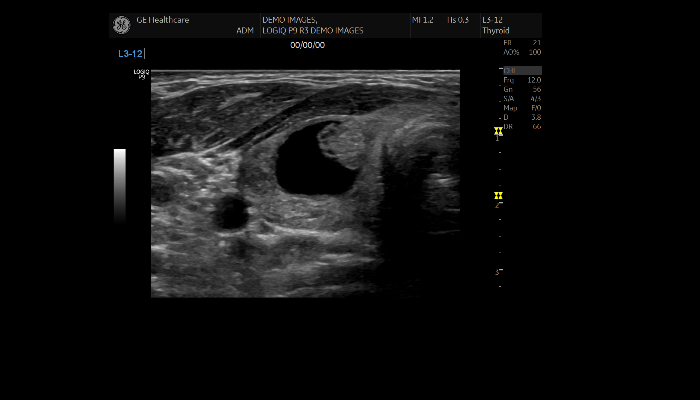

エコー検査装置 エコー検査装置GE社製エコー検査装置 心臓エコー 心臓心臓の動きや心臓弁膜症を調べます。 乳腺エコー 乳腺高濃度乳房の方はマンモグラフィでは病気が見つけにくいことがあります。エコーと併せて評価をお勧めします。 腹部エコー 腹部肝臓、胆嚢、膵臓、腎臓、脾臓など腹部の重要臓器を調べます。 頸部エコー 血管頸動脈の狭窄や下肢の静脈の流れを見ます。脳梗塞や深部静脈血栓症のリスクを調べます。 甲状腺エコー 甲状腺甲状腺腫瘍やバセドウ病など甲状腺疾患を調べます。